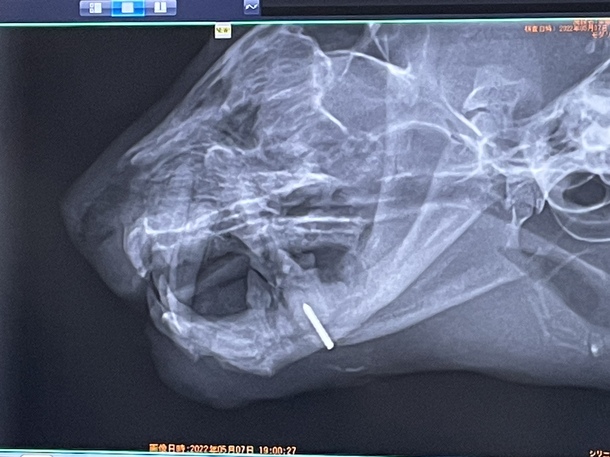

下顎のプレート等の固定具を外しましたが、1箇所だけボルトで支えています。(写真の白い線の様なものがそうです)

そのボルトのせいなのかはまだ不明なのですが、そのあたりから涎のような膿のようなものが出ていて、毎日消毒しています。

全体的に見て、顎が形成され両顎で食事も少しずつ上手く食べられるようになってきましたが

今後の経過により、また手術をしてこのボルトを抜くかも知れないという事です。